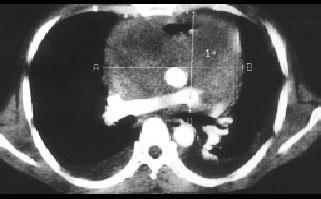

问题 35岁男性患者,一个月前开始间歇性发热,咳嗽、咳痰,足部肿胀,伴颈静脉怒张,行X线、CT检查如图所示,请选择正确的答案 ( )

选项 A、考虑原发性心包间皮瘤 B、考虑为心包炎 C、CT示示心包内见软组织肿块影 D、CT示心包弥漫性增厚,未见钙化影 E、X线示心影增大

答案 ACDE